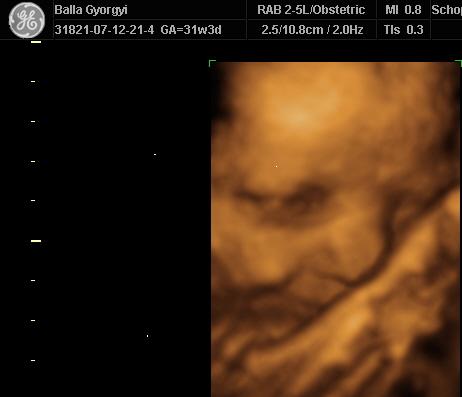

Nagyon szuper az UH kép!

Helyes krapek már most Soma!

:D És nagyon örülök, hogy befordult! Próbálj megnyugodni, tudom, hogy nehéz, de koncentrálj arra, hogy nem lesz semmi baj. BIZTOS, hogy minden rendben lesz!